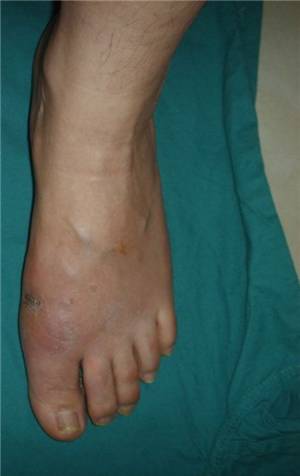

微创矫形方法术前(左)术后(右)对比